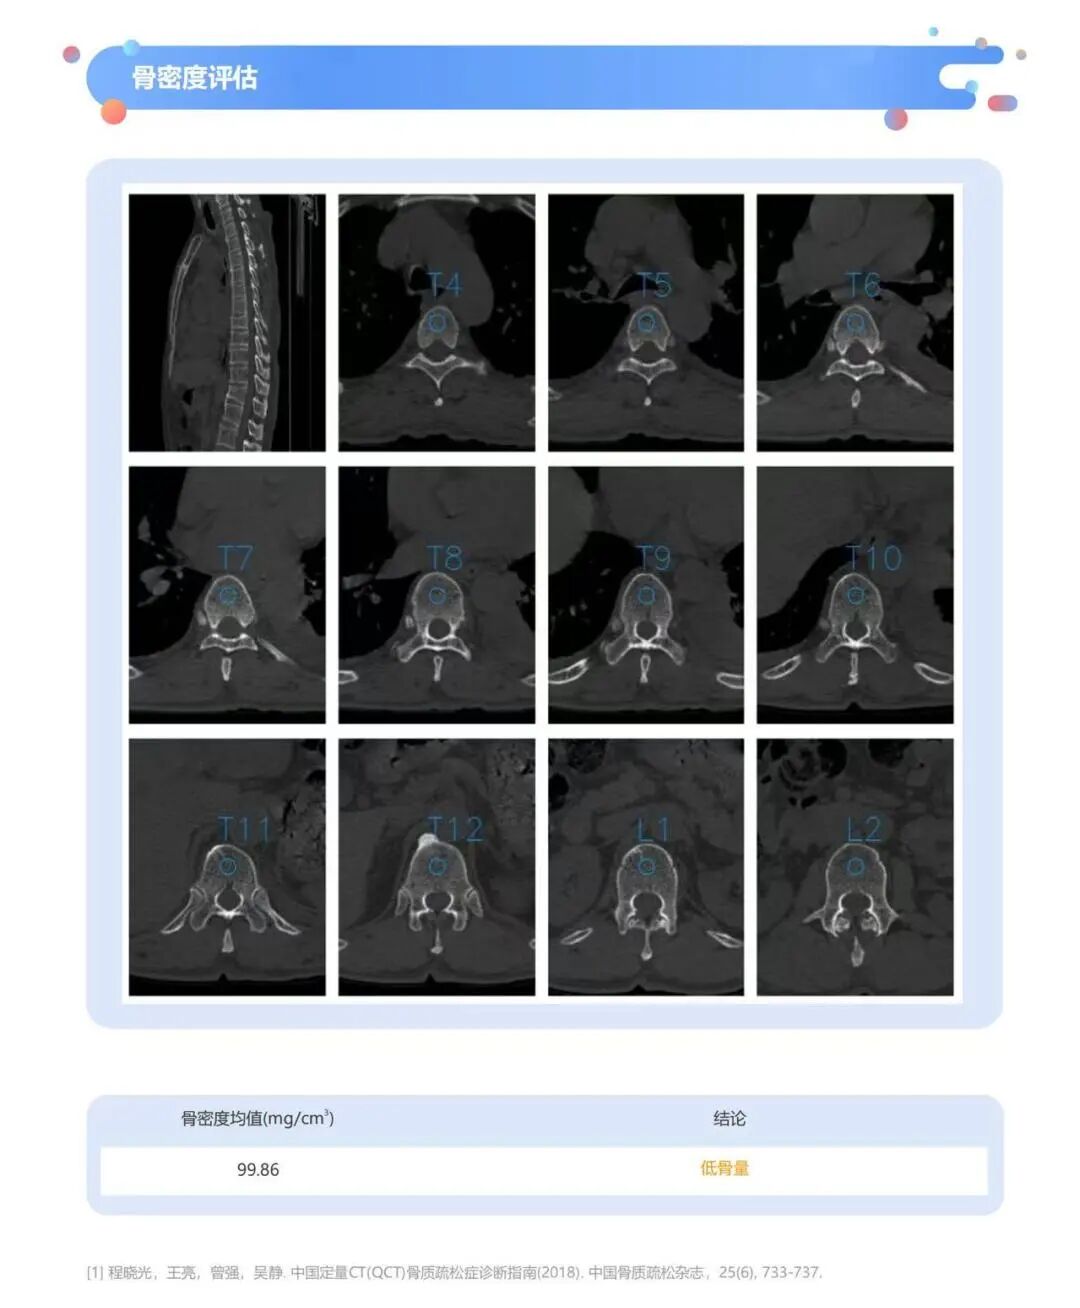

2025 年版《成人健康體檢項(xiàng)目推薦指引》明確:40 歲以上人群常規(guī)體檢新增骨密度檢測項(xiàng)目,體脂率、肌肉脂肪分布情況也納入檢查,且定量 CT(QCT)被列為骨密度檢測優(yōu)先推薦。 健培啄醫(yī)生胸部CT一檢多篩無需額外掃描,依托常規(guī) CT 影像即可完成骨密度檢測,實(shí)現(xiàn) “篩 - 診 - 評” 一體化,為 40 + 人群骨健康管理及骨質(zhì)疏松等慢性病風(fēng)險(xiǎn)評估,提供高效、精準(zhǔn)的技術(shù)支持,助力落實(shí)科學(xué)健康篩查。

輔助檢查包括:心電圖檢查、放射檢查、超聲檢查、人體成分分析。40歲以上人群,增加肺功能檢查和骨密度檢測。